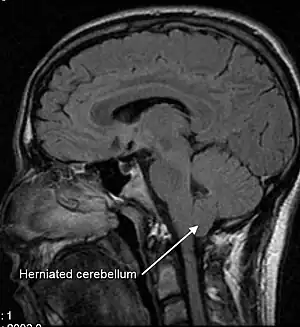

| A sagittal FLAIR MRI scan, from a patient with an Arnold–Chiari malformation, demonstrating tonsillar herniation of 7 mm. | |

Diagnosis is made through a combination of patient history, neurological examination, and medical imaging.[20][21] Magnetic resonance imaging (MRI) is considered the preferred imaging modality for Chiari malformation.[22] The MRI visualizes neural tissue such as the cerebellar tonsils and spinal cord as well as bone and other soft tissues. CT and CT myelography are other options and were used prior to the advent of MRI, unfortunately the resolution of CT based modalities do not characterize syringomyelia and other neural abnormalities as well.[23]

By convention, the cerebellar tonsil position is measured relative to the basion-opisthion line, using sagittal T1 MRI images or sagittal CT images.[24] The selected cutoff distance for abnormal tonsil position is somewhat arbitrary, as not every person will be symptomatic at a certain amount of tonsil displacement, and the probability of symptoms and syrinx increases with greater displacement; however, greater than 5 mm is the most frequently cited cutoff number, though some consider 3–5 mm to be "borderline"; pathological signs and syrinx may occur beyond that distance.[24][25][26] One study showed little difference in cerebellar tonsil position between standard recumbent MRI and upright MRI for patients without a history of whiplash injury.[18] Neuroradiological investigation is used to first rule out any intracranial condition that could be responsible for tonsillar herniation. Neuroradiological diagnostics evaluate the severity of crowding of the neural structures within the posterior cranial fossa and their pressure against the foramen magnum. Chiari 1.5 is a term used when both brainstem and tonsillar herniation through the foramen magnum are present.[27]